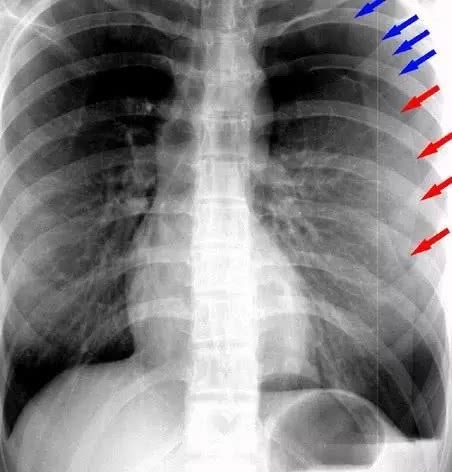

肺部影像显示,小明的右侧肺部气胸已经非常明显,肺大疱也出现破裂,河南省人民医院胸外科主任魏立介绍说,胸膜腔是肺脏和胸壁之间的一个潜在的腔隙,当某些诱因如过度劳累紧张时,容易引起肺脏表面肺大疱破裂,空气经肺表面破口进入胸腔并压缩肺脏形成自发性气胸。